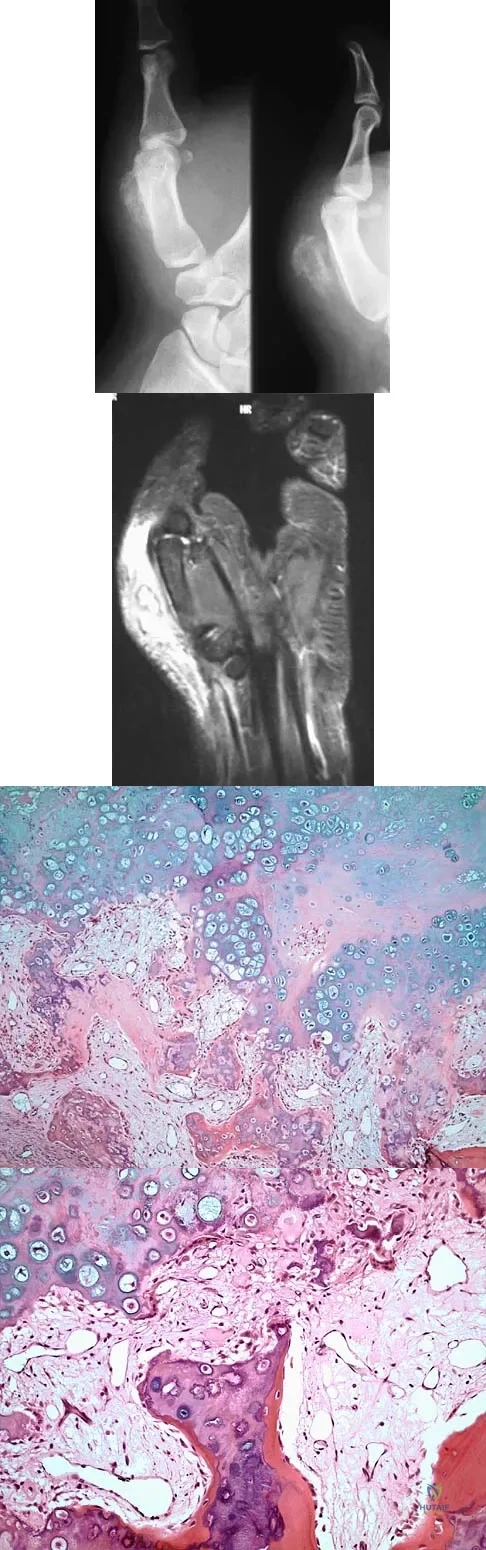

A 10-year-old girl reports activity-related bilateral arm pain. Examination reveals no soft-tissue masses in either arm, and she has full painless range of motion in both shoulders and elbows. The radiograph and bone scan are shown in Figures 20a and 20b, and biopsy specimens are shown in Figures 20c and 20d. What is the most likely diagnosis?

Detailed Explanation

A 65-year-old man has a painful mass of the middle finger. A clinical photograph, lateral radiograph, coronal MRI scan, and biopsy specimen are seen in Figures 20a through 20d. What is the most likely diagnosis?

Explanation

An 18-year-old man has had an enlarging mass in his hand for the past 3 months. Radiographs, an MRI scan, and biopsy specimens are shown in Figures 54a through 54d. What is the most likely diagnosis?

Explanation